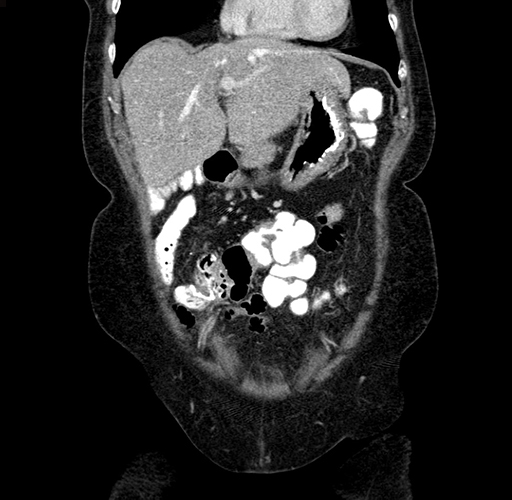

Pre-Chemo: Coronal Venous